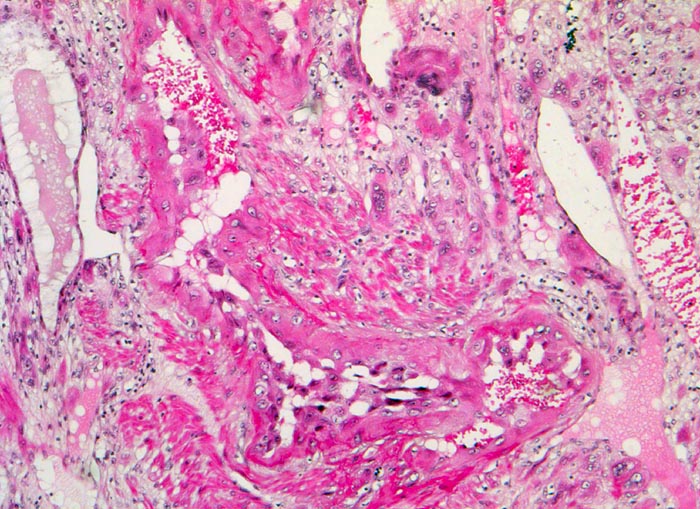

PathoPic – image database / PathoPic ID 5206 - Gravidität

Gravidität

Plazenta

Zytotrophoblastzellen des extravillösen Zytotrophoblasten mit grossen hyperchromatischen Kernen invadieren nicht nur das Myometrium, sondern auch die Spiralarterien der Dezidua. Fetale Zellen sind im Lumen der mütterlichen Spiralarterie nachweisbar.

11. Schwangerschaftswoche. Normale Schwangerschaft

Histologie

50